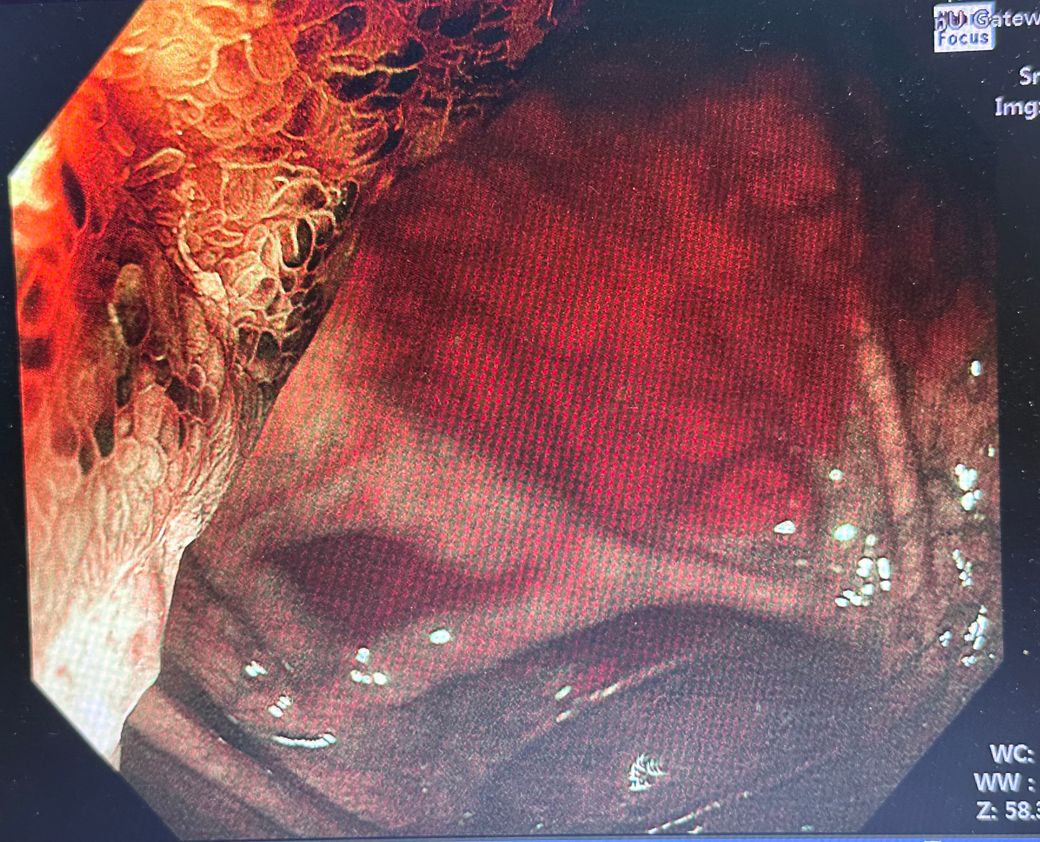

안녕하세요 오늘 내시경을 했는데 사진과 같은 부분이 나왔습니다..

제가 평소에 보던 내시경이랑은 좀 많이 다른 색깔인데 혹시 무엇일까요..

암일 가능성도 있을까요...?

올려주신 사진은 대장내시경 중 맹장과 회맹판 일부를 협대역 영상으로 가시광선을 투과하는 필터를 이용해 점막 표면과 미세혈관의 구조를 살피는 검사 방법입니다